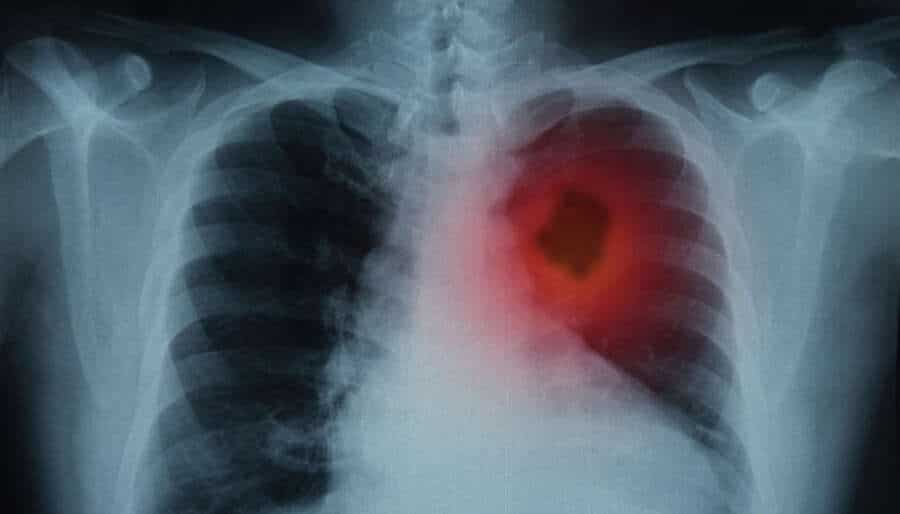

Κάπου εκεί ήρθε η αταξία στη ζωή μου. Μια επίσκεψη στο γιατρό μου που μου ανέτρεψε τα πάντα. Καρκίνος στους πνεύμονες, 4ο στάδιο. Δηλαδή ο καρκίνος είναι σε προχωρημένο στάδιο, έχει εξαπλωθεί σε άλλα όργανα και σημεία του σώματος μου. Δεν υπάρχει επιστροφή. Αν ακολουθήσω κάποια θεραπεία θα ζήσω περίπου ένα χρόνο. Αν όχι μου απομένουν 6 μήνες ζωής.

Είναι σημαντικό να αναφέρω ότι δεν είμαι καπνιστής, δεν ήμουν ποτέ καπνιστής. Ούτε η σύζυγος μου ή κάποιος άλλος στο σπίτι καπνίζει. Στο κολέγιο και γενικά στο εργασιακό μου περιβάλλον ελάχιστες φορές έχω υπάρξει παθητικός καπνιστής. Όμως έχω καρκίνο στους πνεύμονες και το κατάλαβα όταν ένιωσα πόνους στην πλάτη και στο στήθος.

Όπως έμαθα αργότερα, για τον καρκίνο στους πνεύμονες: Μπορεί να προκληθεί από επικίνδυνες ουσίες όπως ο αμίαντος, το αρσενικό, τα φυτοφάρμακα, τη σκόνη και τις αναθυμιάσεις. Από την ατμοσφαιρική ρύπανση, την έκθεση σε ραδόνιο και σαφώς από το παθητικό κάπνισμα. Λιγότερες οι πιθανότητες για έναν μη καπνιστή, όμως ο κίνδυνος παραμονεύει! Η έκθεση στην ακτινοβολία, οι πνευμονοπάθειες και οι λοιμώξεις μπορούν επίσης να τον πυροδοτήσουν.